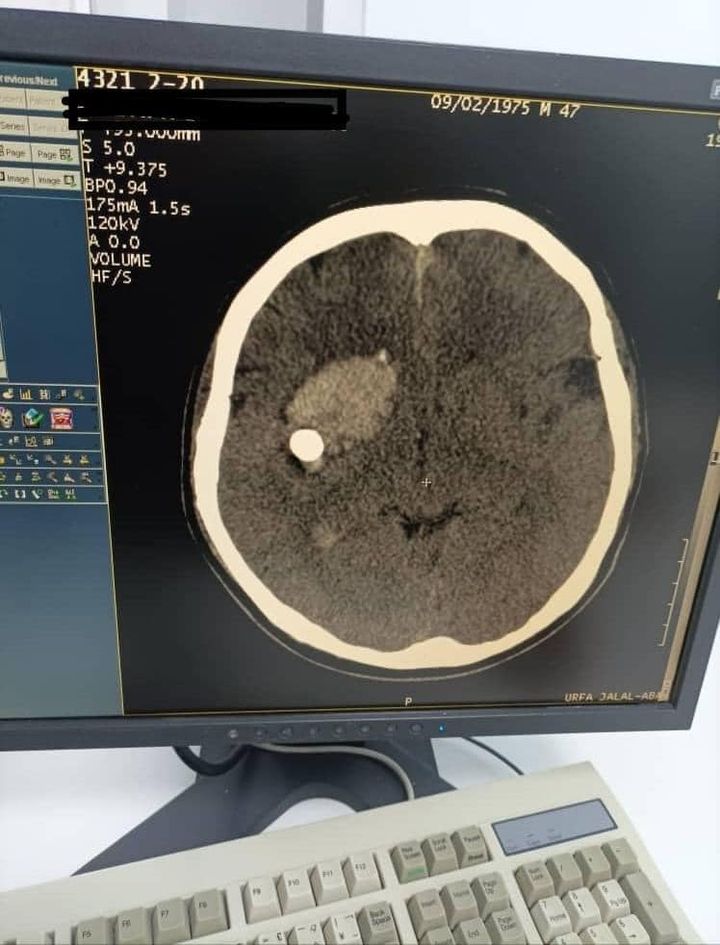

По его данным, пациент поступил с открытым проникающим ранением головы — пуля находилась в лобно-височной доле справа.

«Благодаря кандидату медицинских наук, заведующему нейрохирургическим отделением областной больницы Абдибайиту Идирисову и его команде пациент спасен. Операция прошла успешно, послеоперационное состояние больного оценивается как стабильное», — отметили в Минздраве.